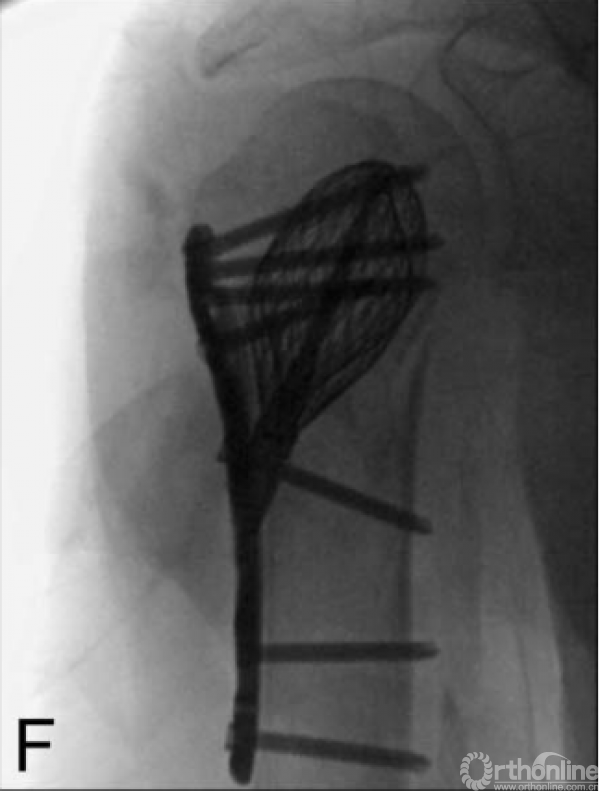

2.2 非典型股骨骨折:Yoon YC[48]介绍了通过矫正截骨、髓内钉可附加钢板强化固定治疗前外侧弓角度增加引起的不完全非典型股骨骨折治疗方法(图7)。20例股骨中有19例在平均24.9周内实现了初次骨愈合。2例延迟愈合,分别于36周和40周愈合。侧弯角度、前弯角度和股骨远端外侧角术后均有显著改善。1例骨不连,附加钢板强化、未植骨后愈合。

图7 Yoon YC研究:骨扫描见不全骨折,截骨后髓内钉固定,6个月后骨折愈合